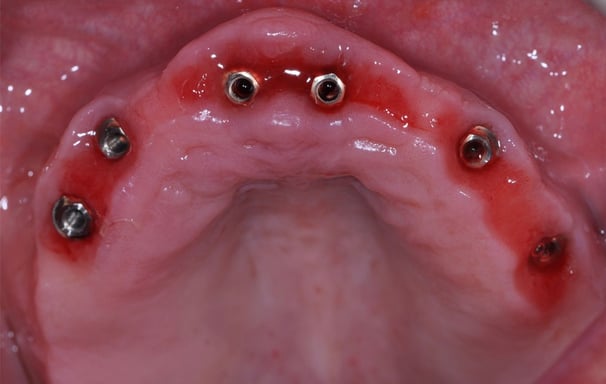

Tratamiento de enfermedades periimplantarias

Se refiere a la atención y manejo de enfermedades que afectan los tejidos alrededor de los implantes dentales, como la mucositis y la periimplantitis.

Manejo de mucositis periimplantaria

Se trata de la inflamación de los tejidos alrededor de un implante dental sin pérdida ósea significativa. Incluye limpieza y cuidado para evitar que la inflamación progrese a periimplantitis.

Tratamiento de periimplantitis

Es una infección que afecta los tejidos alrededor de un implante dental, causando pérdida ósea y posible fracaso del implante. El tratamiento incluye limpieza profunda y, en algunos casos, cirugía.

Mantenimiento de implantes dentales

Consiste en el seguimiento regular de los implantes dentales para asegurar su funcionamiento adecuado y prevenir problemas como la mucositis o la periimplantitis.